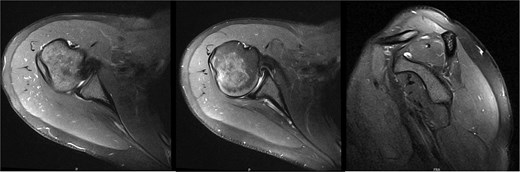

At 9.5 years, she presented reporting recurrent, progressive shoulder weakness and pain during external rotation during self-directed physiotherapy. There was visible atrophy of the right infraspinatus (Fig. 4). She had full symmetrical shoulder range of motion, with 4/5 strength of the right infraspinatus and a markedly weak Hornblower’s test.

Nine and half years after decompression, the patient presented with palpable and visible atrophy of the right infraspinatus.

New MRI arthrogram demonstrated no evidence of new or worsening SSN compression or other pathology. Imaging demonstrated increased right infraspinatus muscular tissue (Fig. 5), however, with significant continued fatty infiltration and persistent atrophy compared to the contralateral side.

MRI at 9.5 years after decompression demonstrated increased right infraspinatus muscular tissue.